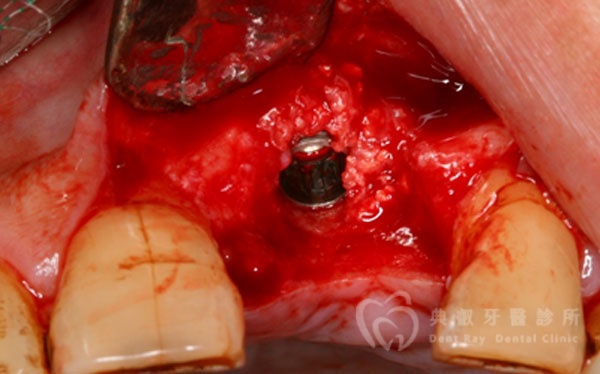

植牙案例四

植牙案例